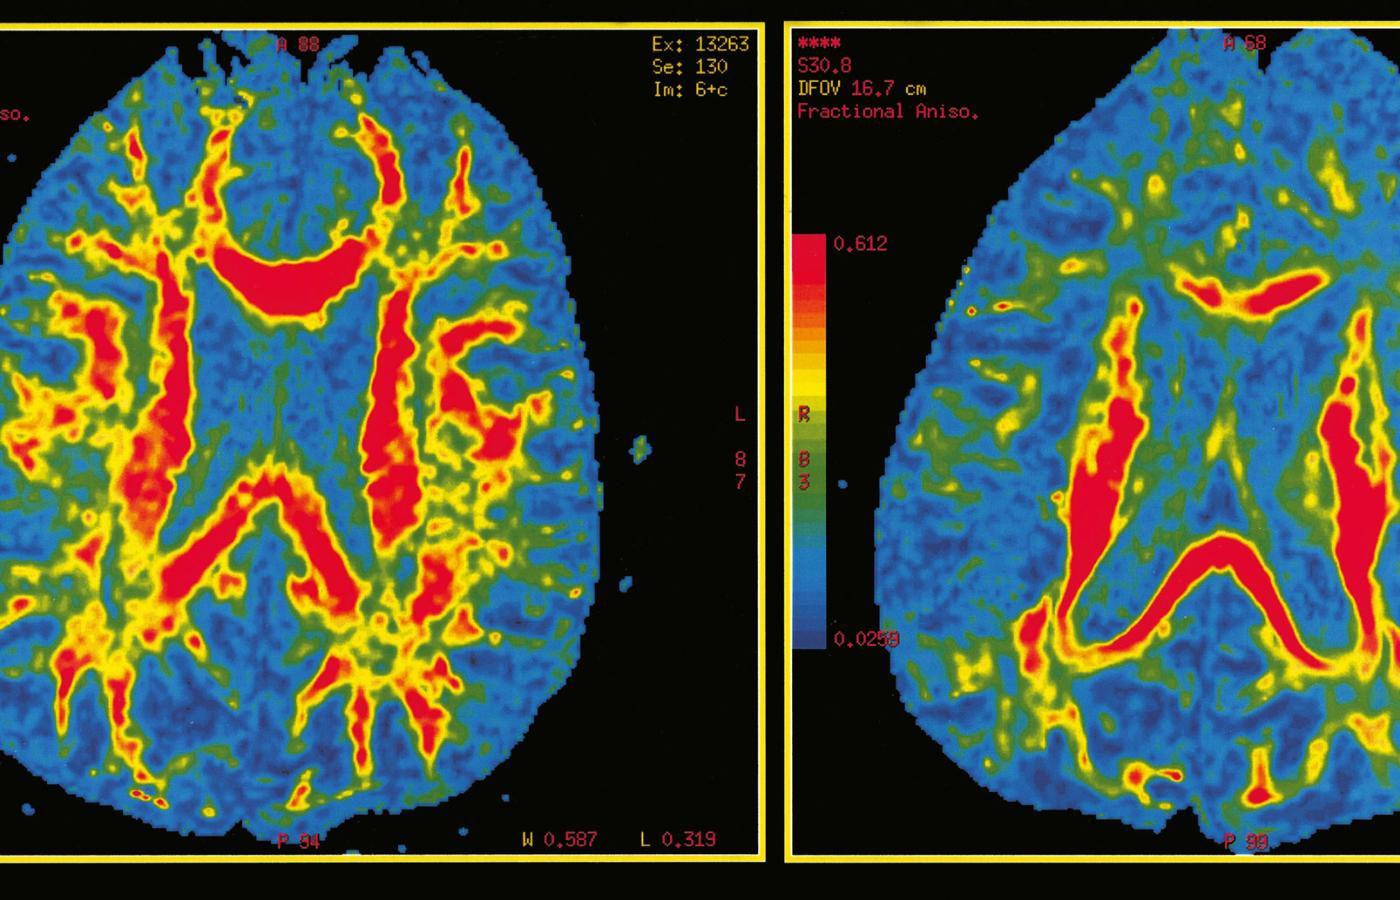

Przykładowe przekroje mózgu uzyskane dzięki rezonansowi magnetycznemu (MRI). Porównanie aktywności mózgu (kolor czerwony) u osoby zdrowej (z lewej) i pacjenta z rozpoznanym alzheimerem. Przykładowe przekroje mózgu uzyskane dzięki rezonansowi magnetycznemu (MRI). Porównanie aktywności mózgu (kolor czerwony) u osoby zdrowej (z lewej) i pacjenta z rozpoznanym alzheimerem. Universal Images Group / Getty Images